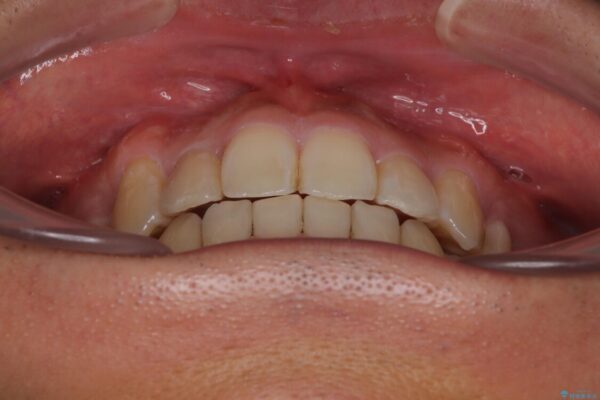

八重歯はきれいに整い、前歯もバランスよく収まり、横顔のラインも自然に改善されました。

治療後、患者様は「思い切り笑えるようになった」と大変喜んでくださいました。

治療後

• 八重歯と前歯のガタガタを抜歯矯正で治療|クリアブラケット使用例 治療後画像